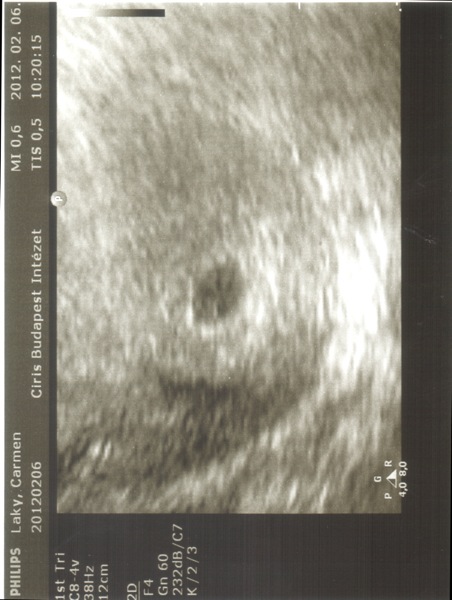

Beszkenneltem az UH képeket:) nem tudom, mennyi fog belőle látszani.

Kép

Kép [/img]

Süti, tök jó a két pöttyös kép, tényleg olyan, mint egy UHU :)

Gyönyörűek a pöttyeid! Örülök, hogy minden oké!